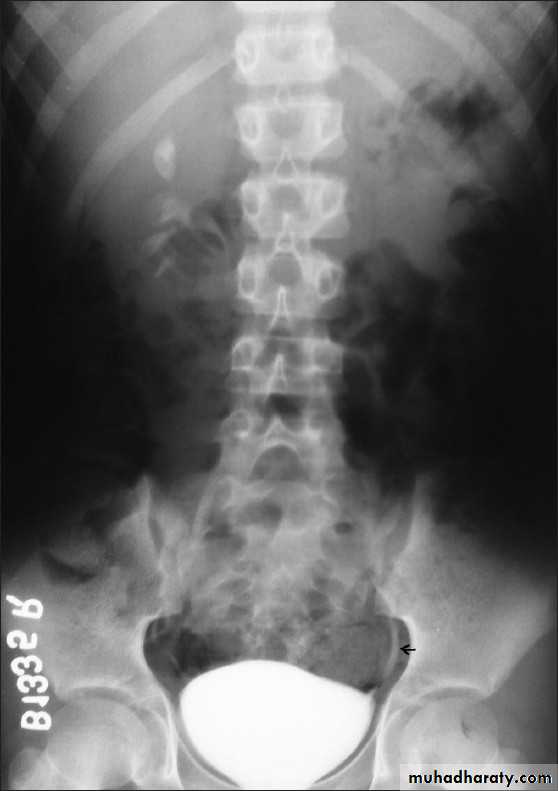

Horse shoe kidney -Kidneys may fail to separate.

-Almost invariably the lower poles remain fused.

-The kidneys axes are more parallel to the spine and malrotated.

-Diagnosis can be made by plain x-ray in some cases.

IVU shows

1. The kidneys at low position .

2.Close to the spine with long axis parallel to the spine .

3. Malrotation manifested by medially directed calyces.

4- The renal pelvis and ureters are anterior and lateral in position .